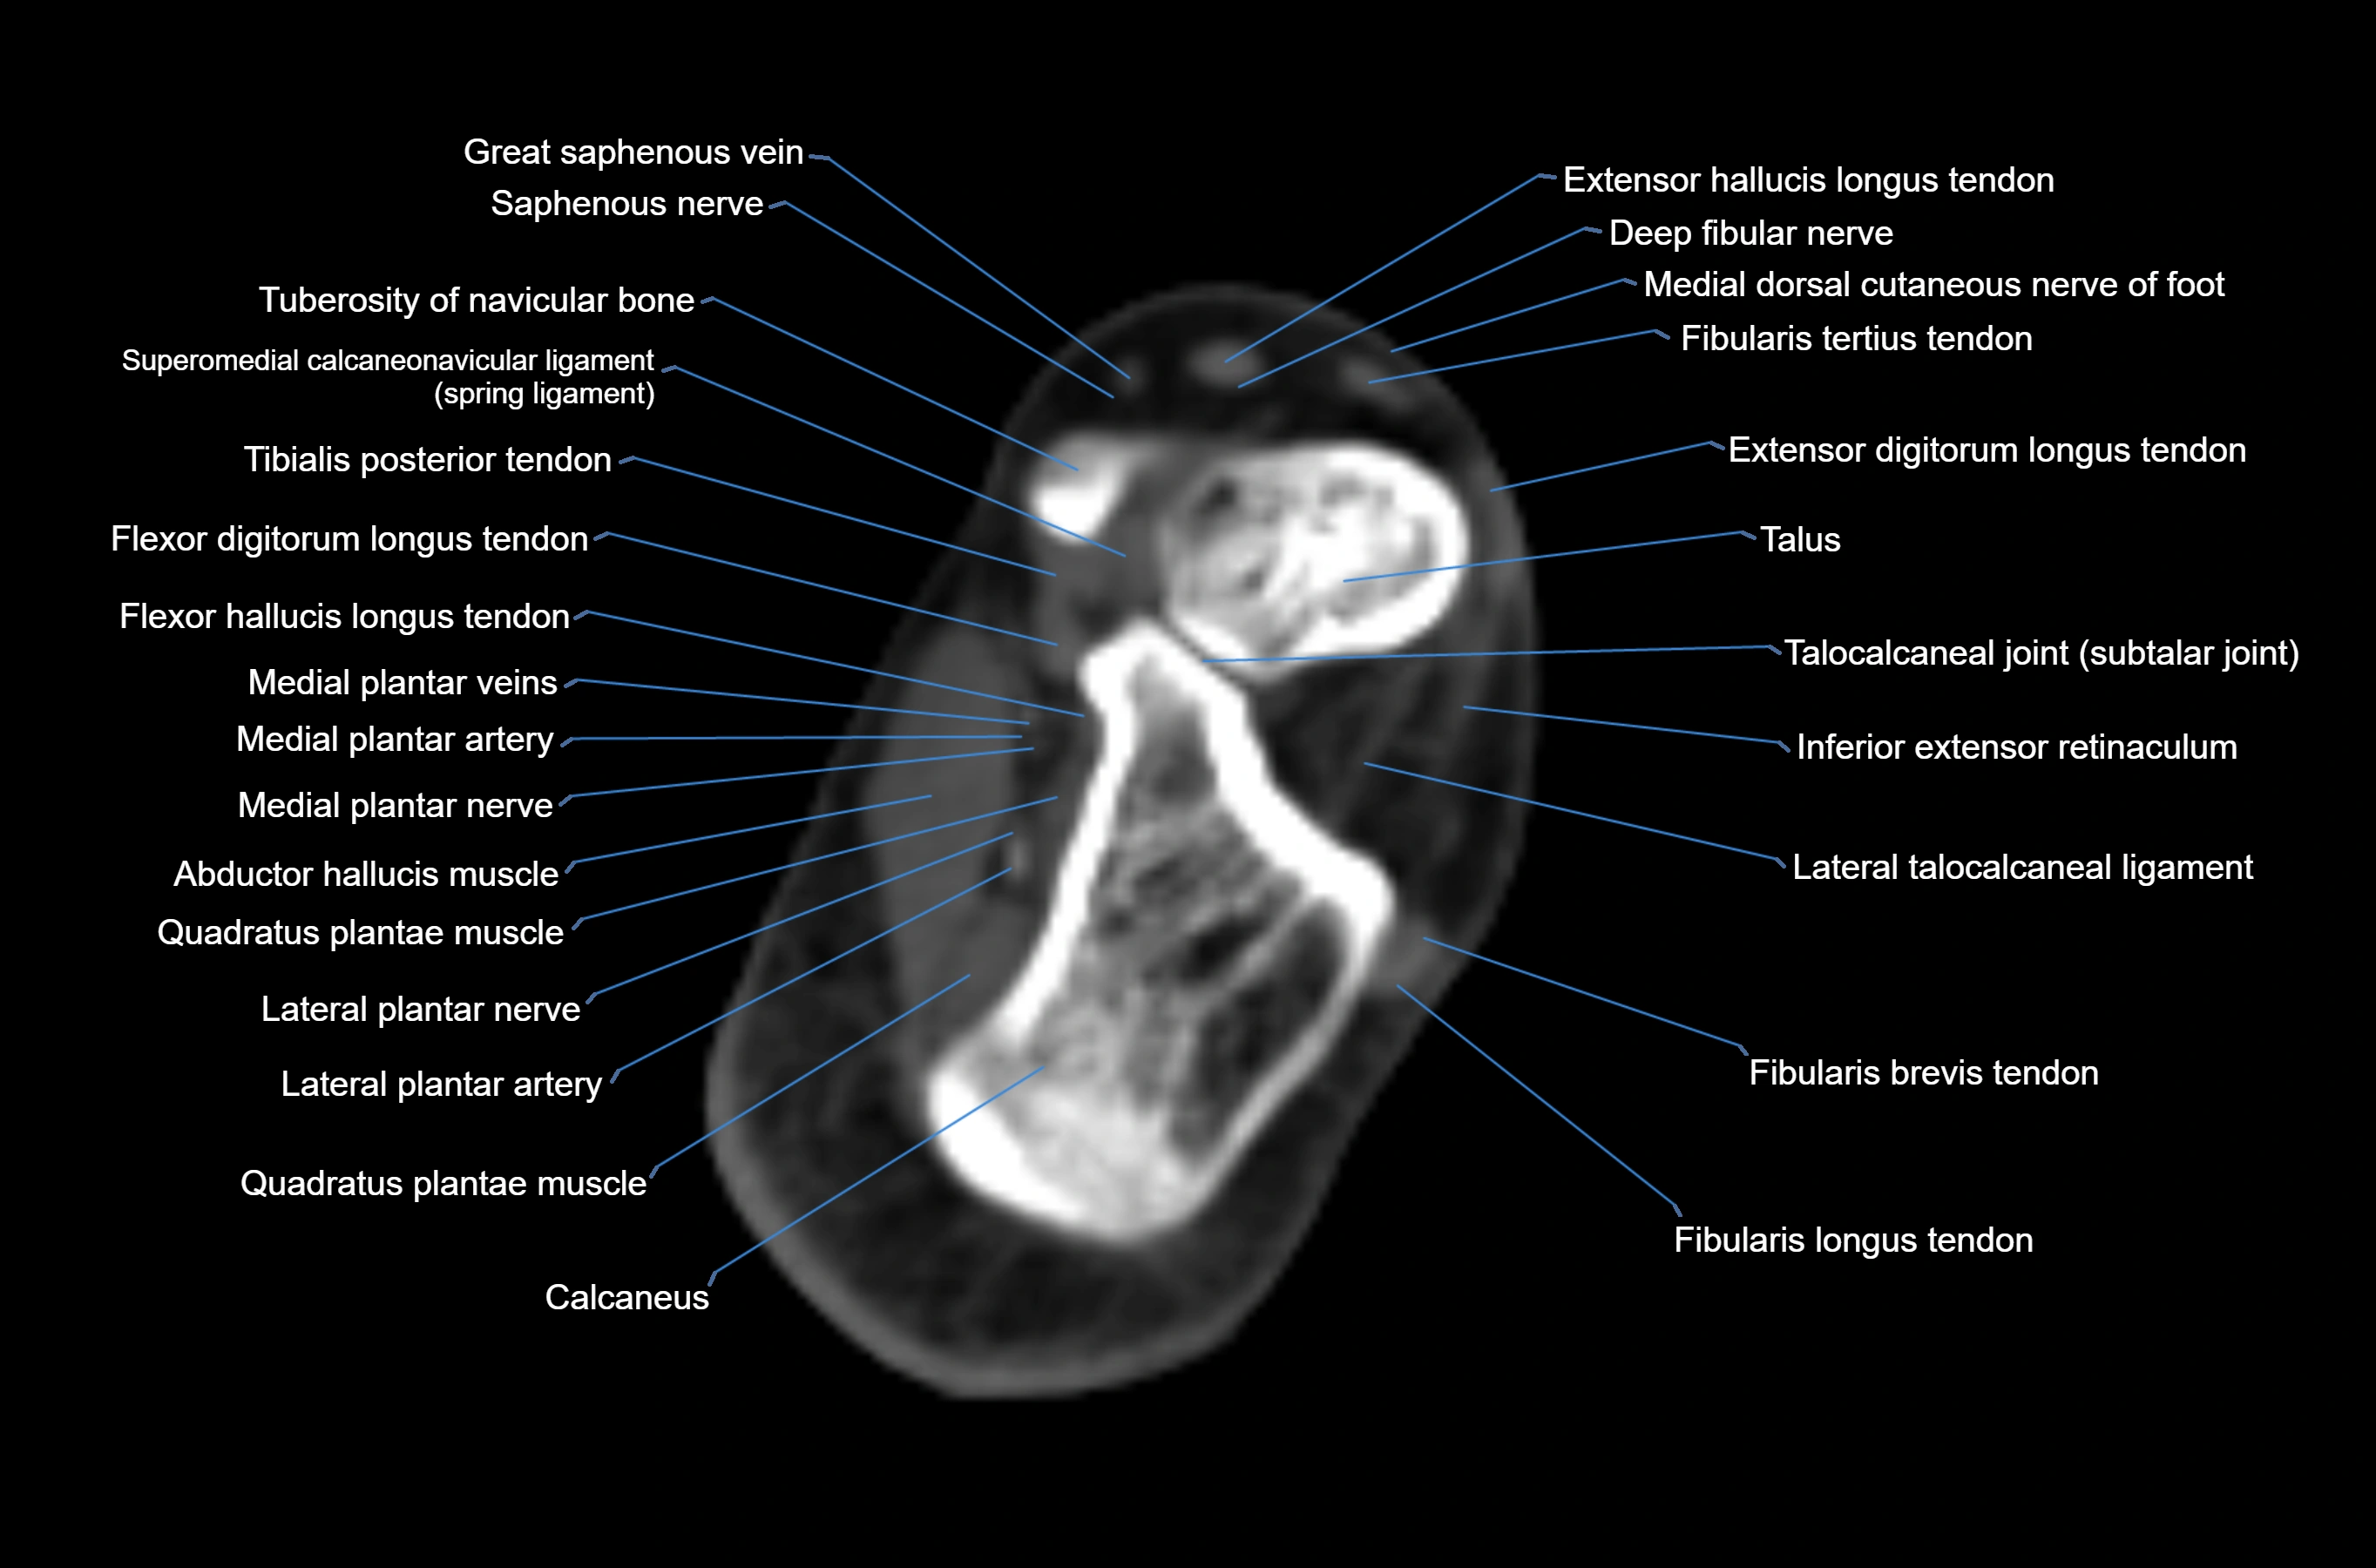

CT image